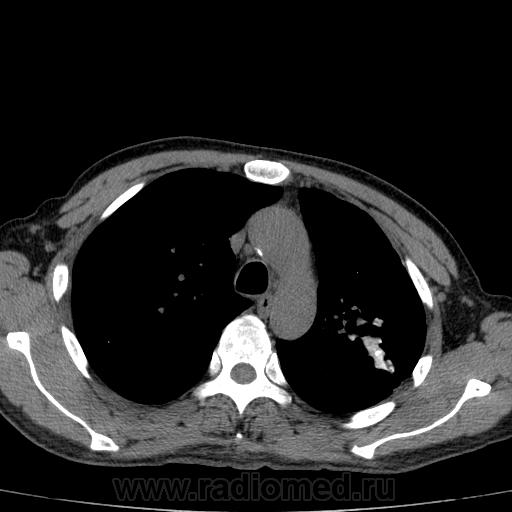

Рецидив туберкулеза?

Больной лечился по пневмонии. На КТ- контроле данные за рецидив туберкулеза (снят с учета в 10 году, асоциальный).

Состоял на учете по поводу фиброзно-кавернозного?

Нет, итл в/д левого л-го. Подняла архив, процесс был слева. Полость появилась справа, значит рецидив. Снят в прошл году с учета.